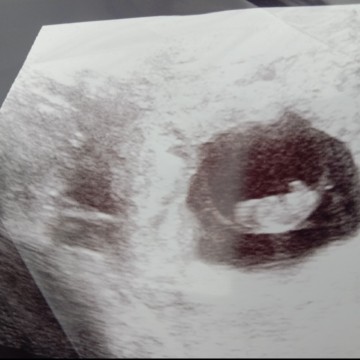

ถ้านับถึงตอนนี้ฉันตั้งครรภ์ได้ 11 สัปดาห์แล้ว ย้อนกลับไปเมื่อวันที่13ตุลาคม ในช่วงเช้าฉันได้พบว่าฉันตั้งครรภ์ วันที่19ตุลาคมได้พบคุณหมอครั้งแรกคุณหมอตรวจร่างกายแล้วนัดไปฝากครรภ์ในวันที่16พฤศจิกายน แต่ระหว่างก่อนถึงวันนัดฝากครรภ์ ฉันเกิดอาการปวดท้อง ปวดหัวหน่าว ปวดหน่วงบริเวณอวัยวะเพศลามไปจนถึงหลังและมีมูกเลือดออกมานิดหน่อย ฉันจึงไปพบหมอ หมออัลตร้าซาวด์ให้บอกยังปกติดีมีหัวใจเต้นแล้วนะ วันนั้นเป็นวันแรกที่ฉันเห็นหัวใจของลูกเต้น ฉันดีใจจนพูดไม่ถูก จนถึงวันนัดฝากครรภ์หมอก็อัลตร้าซาวด์ให้อีก1รอบ แจ้งอายุครรภ์ 8+2 สัปดาห์ แต่หมอบอกว่าเห็นหัวใจไม่ค่อยชัดเท่าไร และไม่คอนเฟิร์มว่าจะท้องต่อไหม ตอนนั้นกังวลใจมากแต่ก็ยังคิดในแง่ดี 2สัปดาห์ต่อมาหมอนัดไปอัลตร้าซาวด์ใหม่ แต่คราวนี้หมอบอกว่าเด็กไม่โตขึ้นเลย ปกติต้อง10+2 สัปดาห์ แต่ตอนนี้ตัวยาวแค่1.67ซม.เท่ากับเมื่อ2สัปดาห์ที่แล้ว แต่ที่สำคัญคือไม่พบหัวใจเต้นแล้ว และพบเลือดในถุงตั้งครรภ์ หมอเลยขอเจาะเลือดดูฮอร์โมนตั้งครรภ์ในวันที่30พ.ย และ2ธ.ค. ผลปรากฎว่าฮอร์โมนตั้งครรภ์ลดลง หมอคอนเฟิร์มว่าแท้งคุกคาม เลยต้องนอนโรงพยาบาลเพื่อที่จะนำเด็กและถุงตั้งครรภ์ออกมา หมอทำการเหน็บยา3เม็ดและงดน้ำงดอาหารแต่ยังไม่มีวี่แววว่าถุงตั้งครรภ์จะหลุดออกมา เลยต้องทำการขูดมดลูก จนตอนนี้ผ่านมา2วันนับตั้งแต่วันที่ลูกไม่อยู่ในท้องของฉัน ฉันรู้สึกเสียใจ และยังสับสนงงงวยกับเหตุการณ์ที่เกิดขึ้น ทุกอย่างมันเกิดขึ้นเร็วมากจนยังไม่ทันได้ทำใจ ณ ตอนนี้ทุกครั้งที่นึกถึงที่ยังคงร้องไห้มีน้ำตาเสมอ รักลูกเสมอนะ ไว้มาเกิดเป็นลูกแม่ใหม่อีกครั้ง ไปสู่ภพภูมิที่ดีนะลูกรัก #แท้งคุกคาม